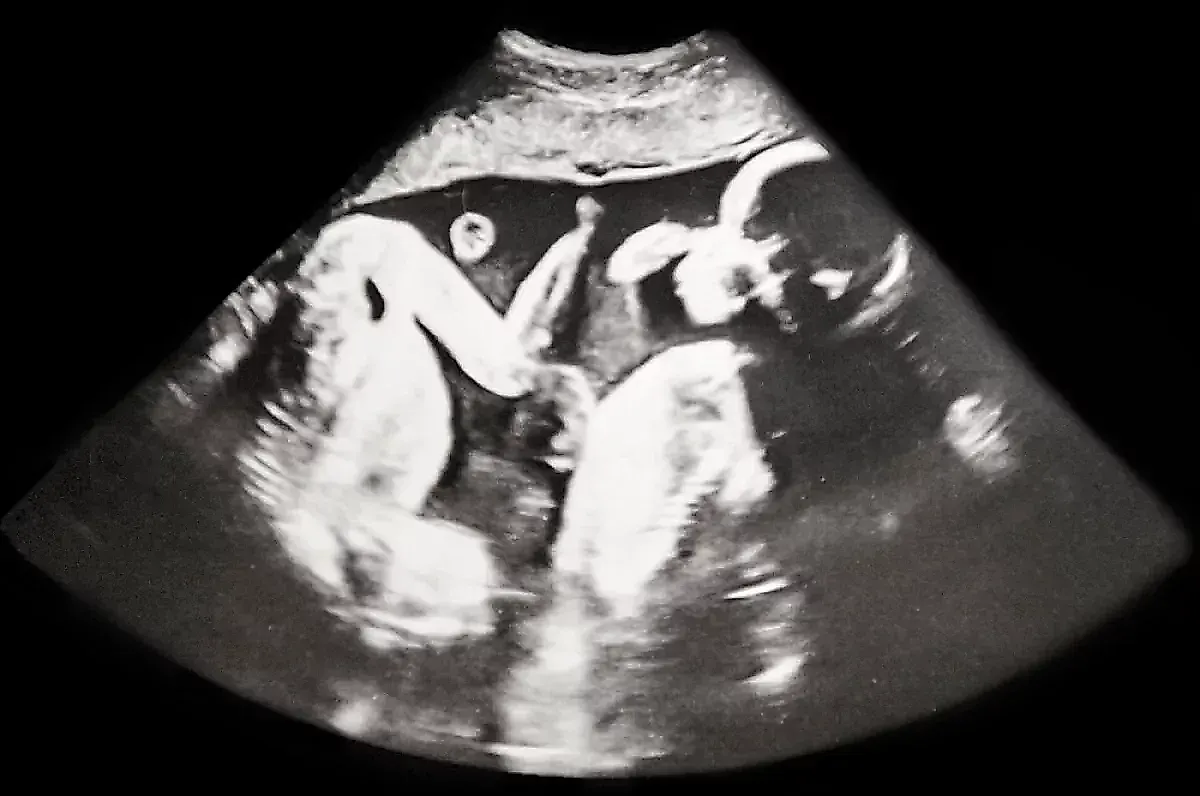

В Санкт-Петербурге произошло уникальное событие, которое стало первым в истории российской медицины: женщина родила сразу четырёх дочек-близняшек. Все девочки — однояйцевые близнецы, что делает этот случай исключительно редким не только в России, но и во всём мире. Малышки появились на свет на 32-й неделе беременности, что для такой сложной многоплодной беременности считается вполне нормальным сроком. Их вес составил от 1360 до 1640 граммов, а рост — от 37 до 41 сантиметра.

Однояйцевые близнецы, как объясняет Дмитрий Шеховцов, возникают в результате деления одной оплодотворённой яйцеклетки (зиготы) на несколько эмбрионов. Для двойни это происходит один раз, а для тройни или четверни — как минимум ещё одно деление. Ключевым фактором здесь является время: в случае петербургской четверни разделение, вероятно, случилось на 4–8-й день после оплодотворения, что привело к формированию монохориальной структуры — общей плаценты для всех плодов.